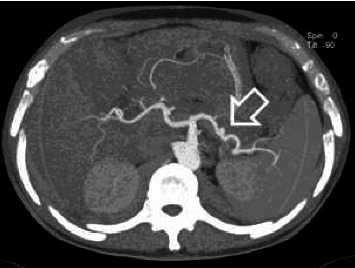

Hemosuccus pancreaticus (HP) is a rare but potentially life-threatening condition, characterized by upper gastrointestinal bleeding from the ampulla of Vater, often originating from a ruptured pseudoaneurysm of the peripancreatic arteries. Despite its rarity, HP presents a diagnostic and therapeutic challenge due to its elusive clinical presentation and complex underlying pathophysiology. In this case report, we presented a compelling instance of HP, diagnosed in a 48-year-old man, complicated with gastrointestinal bleeding and severe anemia successfully managed with urgent endovascular intervention. We highlighted the importance of early recognition, prompt intervention, and interdisciplinary collaboration in achieving favorable outcomes in patients afflicted by this distinctly unusual condition.